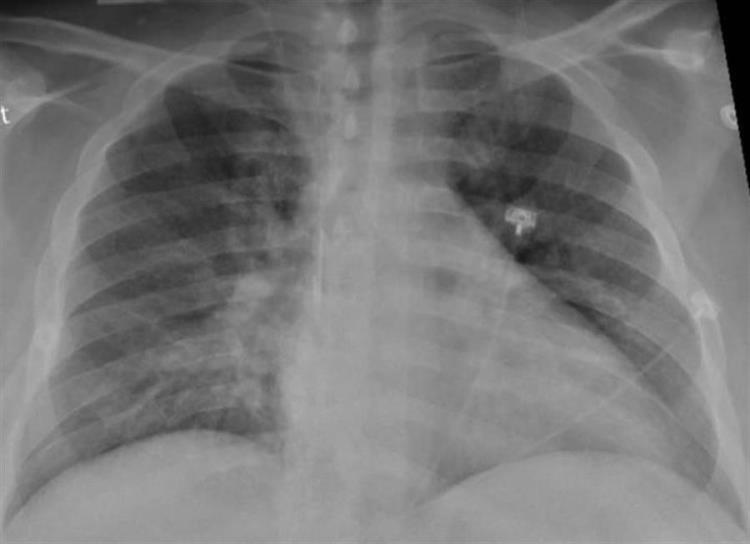

Radiografía de tórax de un paciente de SARS-CoV-2 que muestra debilidad en el lado izquierdo y una neumonía en la parte inferior de los pulmones. EFE/Sociedad Radiológica de Norteamérica